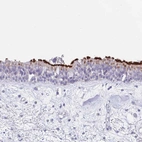

Immunohistochemical staining of human nasopharynx shows strong membranous positivity in respiratory epithelial cells.